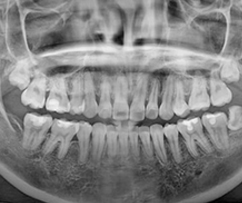

임플란트는 잇몸뼈 속 수많은 혈관과 신경, 주변 치아까지 고려한 철저한 수술계획과 노하우로 안전하게 진행해야 합니다.

3D CT 촬영으로 치아와 치조골의 상태 및

잇몸뼈의 양과 길이 등의 상태를 정확하게

측정하여 세밀한 진단과 시술 전 발생가능한

문제점을 사전에 발견하고 대비하여

진료의 안정성을 높힙니다.

임플란트는 굉장히 세밀한 치료이기 때문에 정밀한 3D 디지털 기술을 접목하면

의료진의 판단에만 의존하던 임플란트 치료를 더욱 정확하게 예측하고 진단하여 오차를 줄일 수 있습니다.